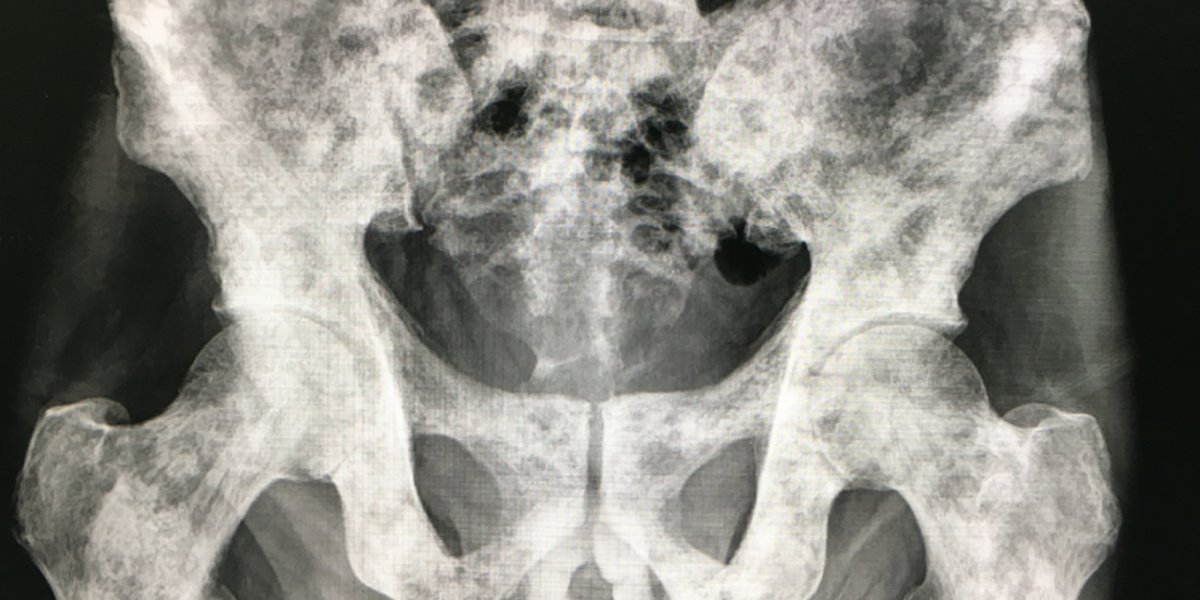

Several interconnected factors explain how a single bone metastasis can be present in your left ischial tuberosity (a part of your pelvis) despite the other findings:

This affinity means bone is a common first site of distant spread for prostate cancer. The metastasis you have is "sclerotic," meaning it's causing new bone formation, which is typical for prostate cancer bone metastases.

Illustration of Bone Metastasis in Prostate Cancer

Conceptual illustration of prostate cancer cells metastasizing to bone.